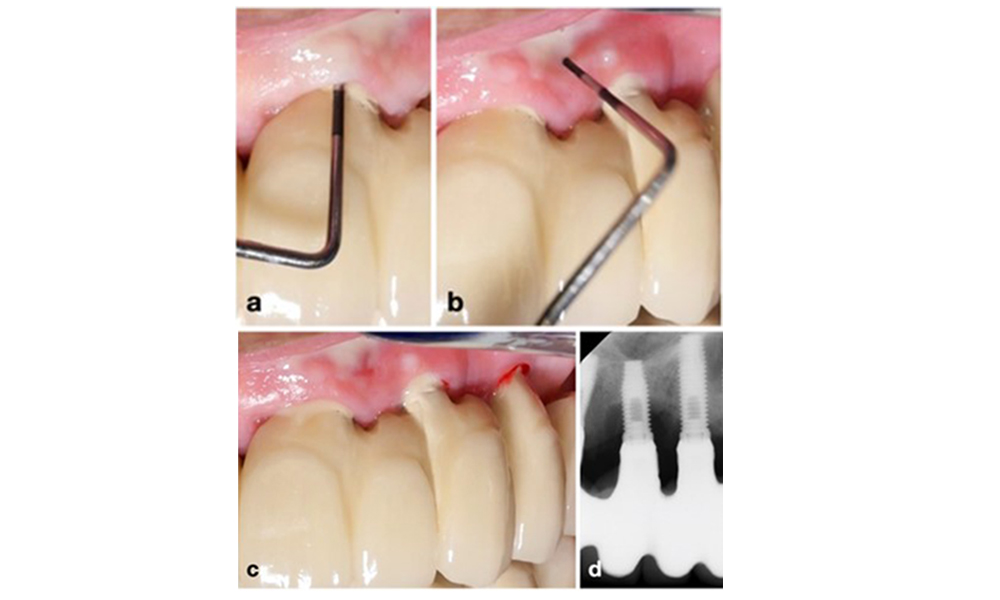

Periimplantitis ist zu erkennen an (1) Entzündungszeichen, vergleichbar einer Mukositis, (2) einem radiologischen Nachweis von Knochenverlust nach Ersteinheilung und (3) der Zunahme der Sondierungstiefe im Vergleich zu Messungen kurz nach dem Einsetzen der prothetischen Rekonstruktion (Abb. 2). Liegen keine früheren Röntgenaufnahmen vor, weisen ein radiologisches Knochenniveau von ≥ 3 mm zusammen mit Sondierungsblutungen und Sondierungstiefen von ≥ 6 mm auf eine Periimplantitis hin.

Der erwartete Knochenverlust nach Ersteinheilung ist auf die marginale Knochen-Remodellierung zurückzuführen und variiert in Abhängigkeit von Faktoren wie Implantatsystem oder Implantattyp.

Ein Knochenverlust von 1–2 mm gilt beispielsweise bei Implantaten auf Knochenniveau mit Außenverbindung allgemein als „normal“ (Abb. 2d, Implantat an Position 23).